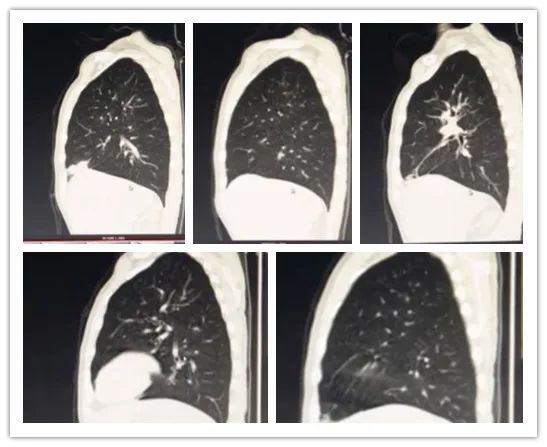

李某,男,26岁,白血病病史,行胸部CT检查,排除肺部浸润情况。

影像所见:

双肺纹理增粗、模糊,双肺见弥漫性斑点状阴影;中肺野见小团片状影,边界尚清,大小约2.1×3.3cm,周围见小斑片模糊影及条索影,邻近胸膜受牵拉,粘膜增厚。

冠状位图像

冠状位见双肺纹理增粗、模糊,双肺见弥漫性斑点状阴影。

矢状位图像

矢状位见双肺纹理增粗、模糊,双肺见弥漫性斑点状阴影。